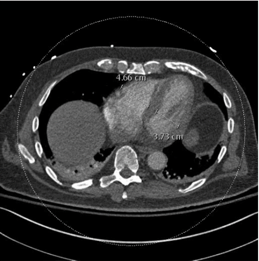

In this study, we aim to initiate the development of Radiology Foundation Model, termed as RadFM.We consider the construction of foundational models from the perspectives of data, model design, and evaluation thoroughly. Our contribution can be concluded as follows: (i), we construct a large-scale Medical Multi-modal Dataset, MedMD, consisting of 16M 2D and 3D medical scans. To the best of our knowledge, this is the first multi-modal dataset containing 3D medical scans. (ii), We propose an architecture that enables visually conditioned generative pre-training, allowing for the integration of text input interleaved with 2D or 3D medical scans to generate response for diverse radiologic tasks. The model was initially pre-trained on MedMD and subsequently domain-specific fine-tuned on RadMD, a radiologic cleaned version of MedMD, containing 3M radiologic visual-language pairs. (iii), we propose a new evaluation benchmark that comprises five tasks, aiming to comprehensively assess the capability of foundation models in handling practical clinical problems. Our experimental results confirm that RadFM significantly outperforms existing multi-modal foundation models. The codes, data, and model checkpoint will all be made publicly available to promote further research and development in the field.